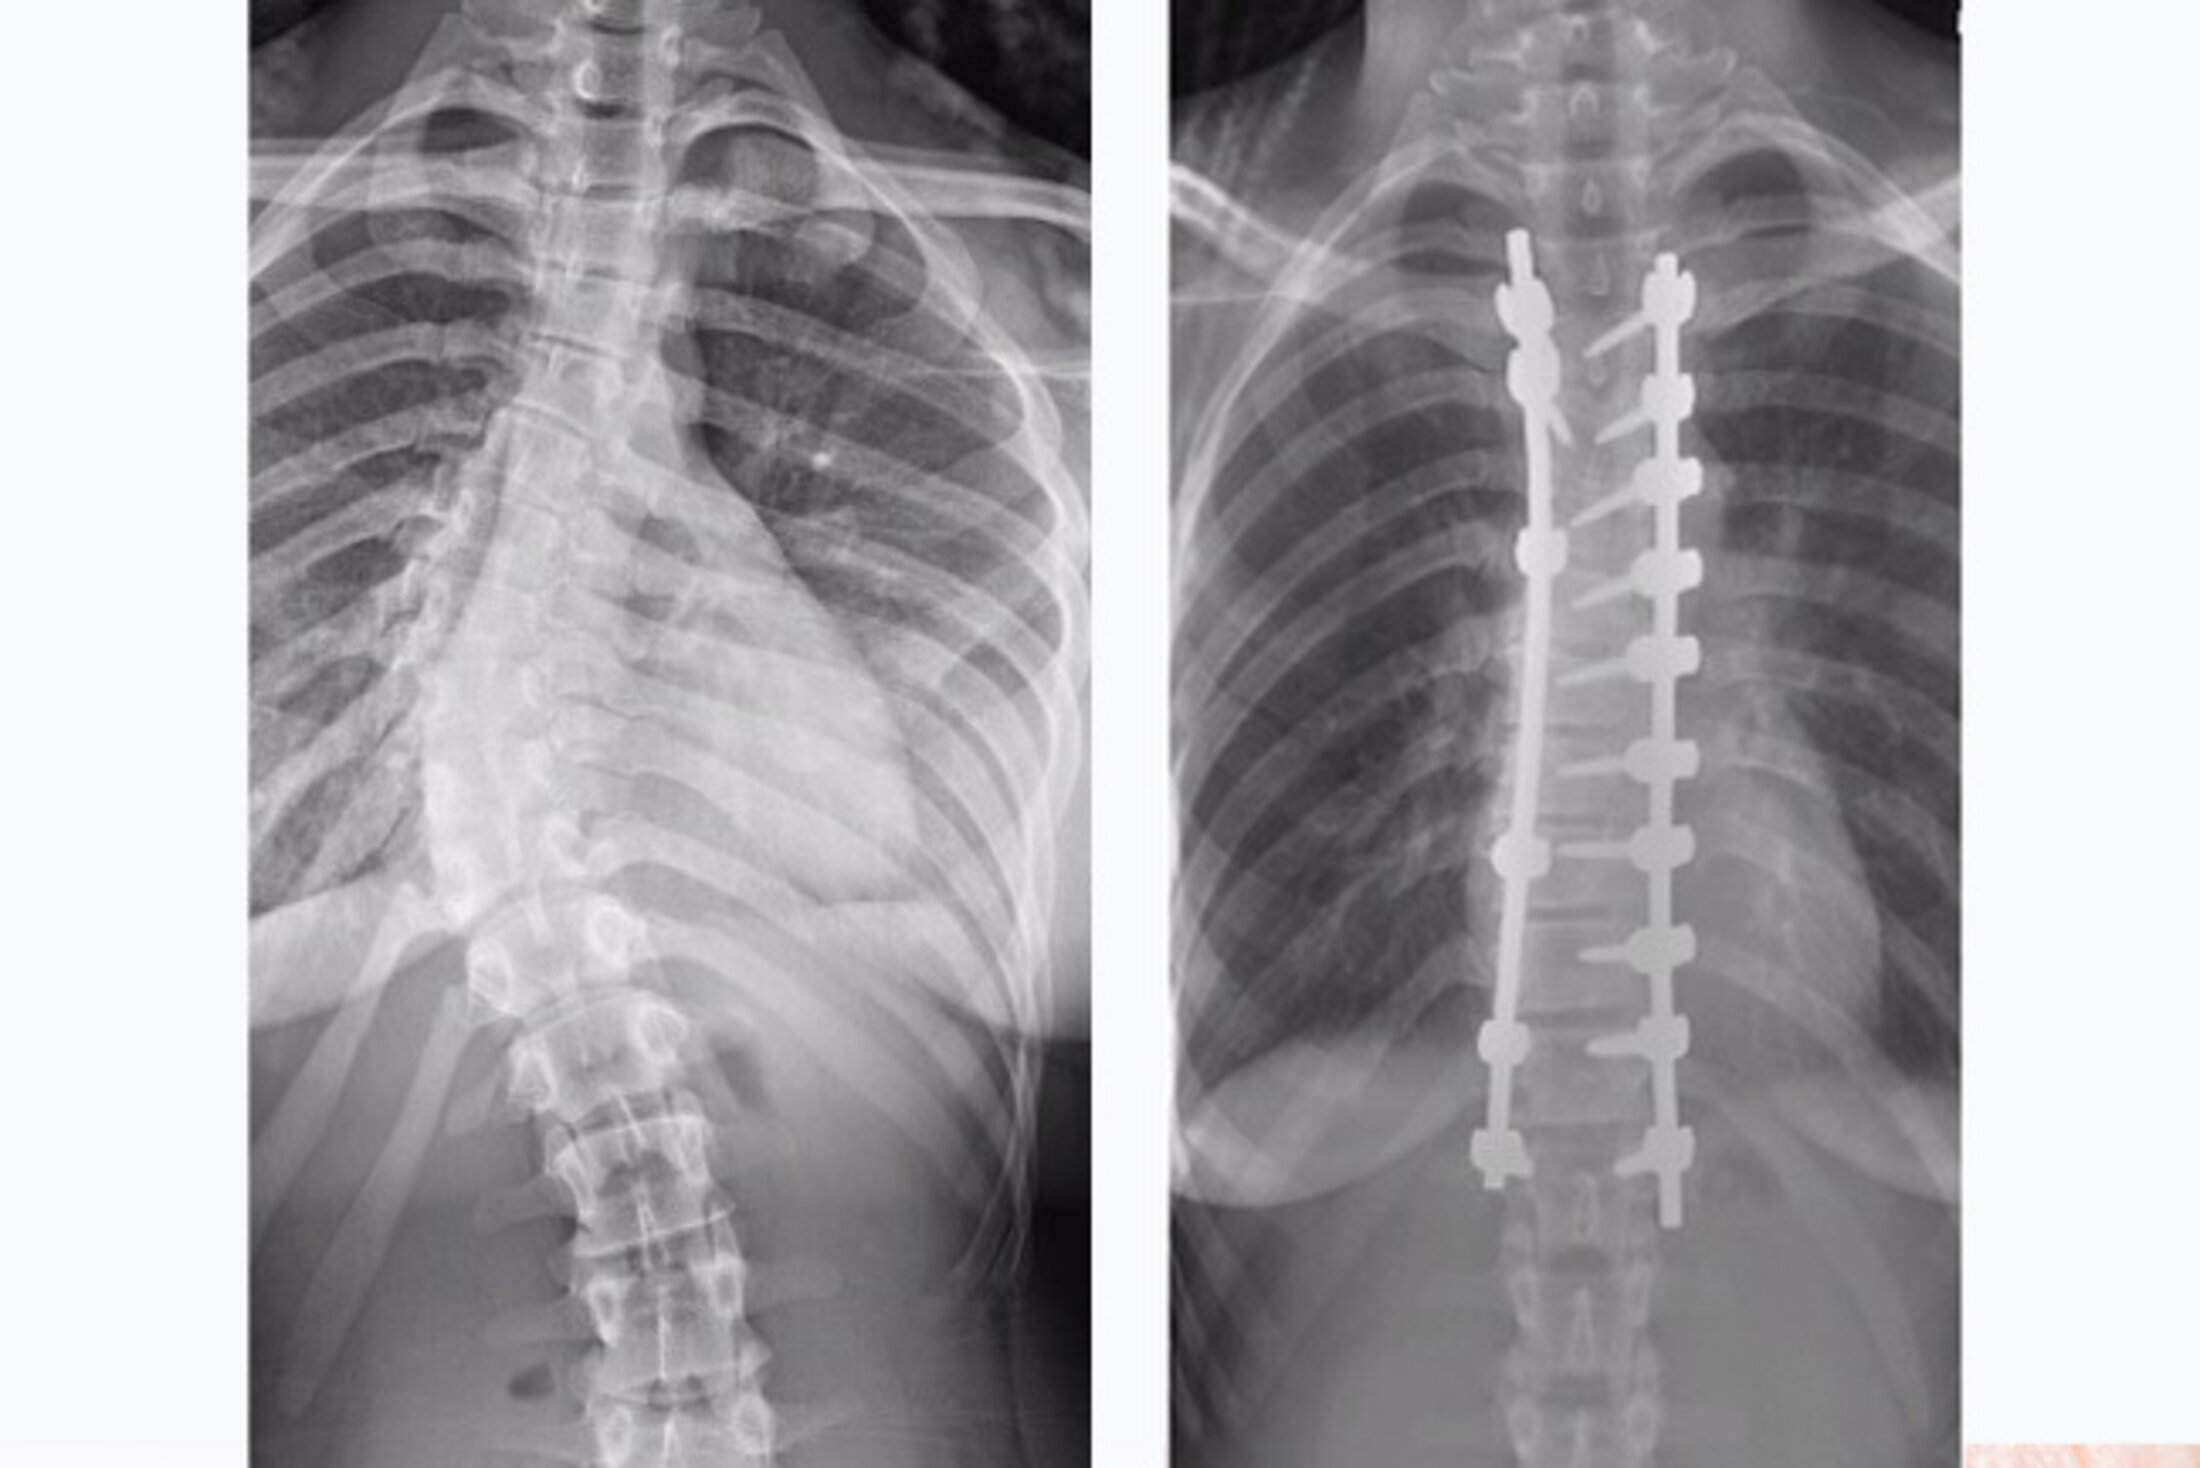

Reitman recently performed a scoliosis deformity correction in a 19-year-old woman who had begun to suffer from pain as a result of her curvature. Her main area of scoliosis was in the thoracic spine, and while the lower curve also had abnormal curvature that area was still mobile and functional.

“We addressed the stiff thoracic curve, and the mobile lower spine should accommodate back to that,” Reitman explained. “Sparing the lower lumbar spine from fusion will help her functionally over the long term.”

The surgery was performed by fusing the lower two thirds of the thoracic vertebrae plus the first lumbar vertebra. Reitman used one side of the spine as the corrective side, inserting screws at each vertebral level to allow him maximal control over the correction. He also inserted implants on the opposite side of the spine, but at a lower density and for support purposes only.